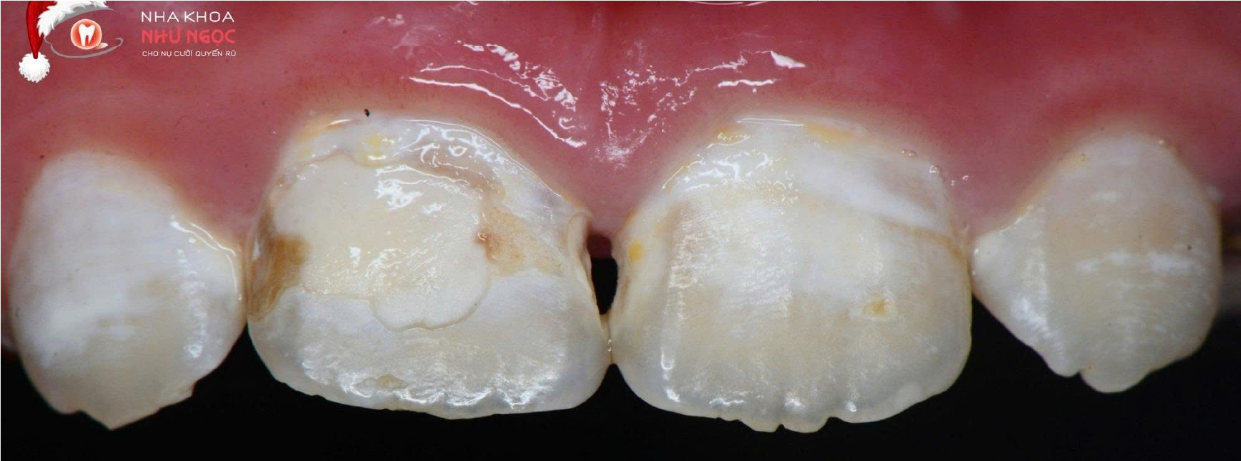

Phục hồi và tạo hình răng

Ứng dụng vật liệu composite nano hoặc công nghệ thẩm thấu nhựa (ICON) để tái tạo cấu trúc răng, phục hồi thẩm mỹ và chức năng ăn nhai tự nhiên.

Hình Ảnh Trước & Sau Điều Trị

Minh chứng rõ ràng cho chất lượng và hiệu quả tại Nha khoa Như Ngọc – nơi mỗi khách hàng đều tìm lại được nụ cười tự tin sau quá trình điều trị và thẩm mỹ răng